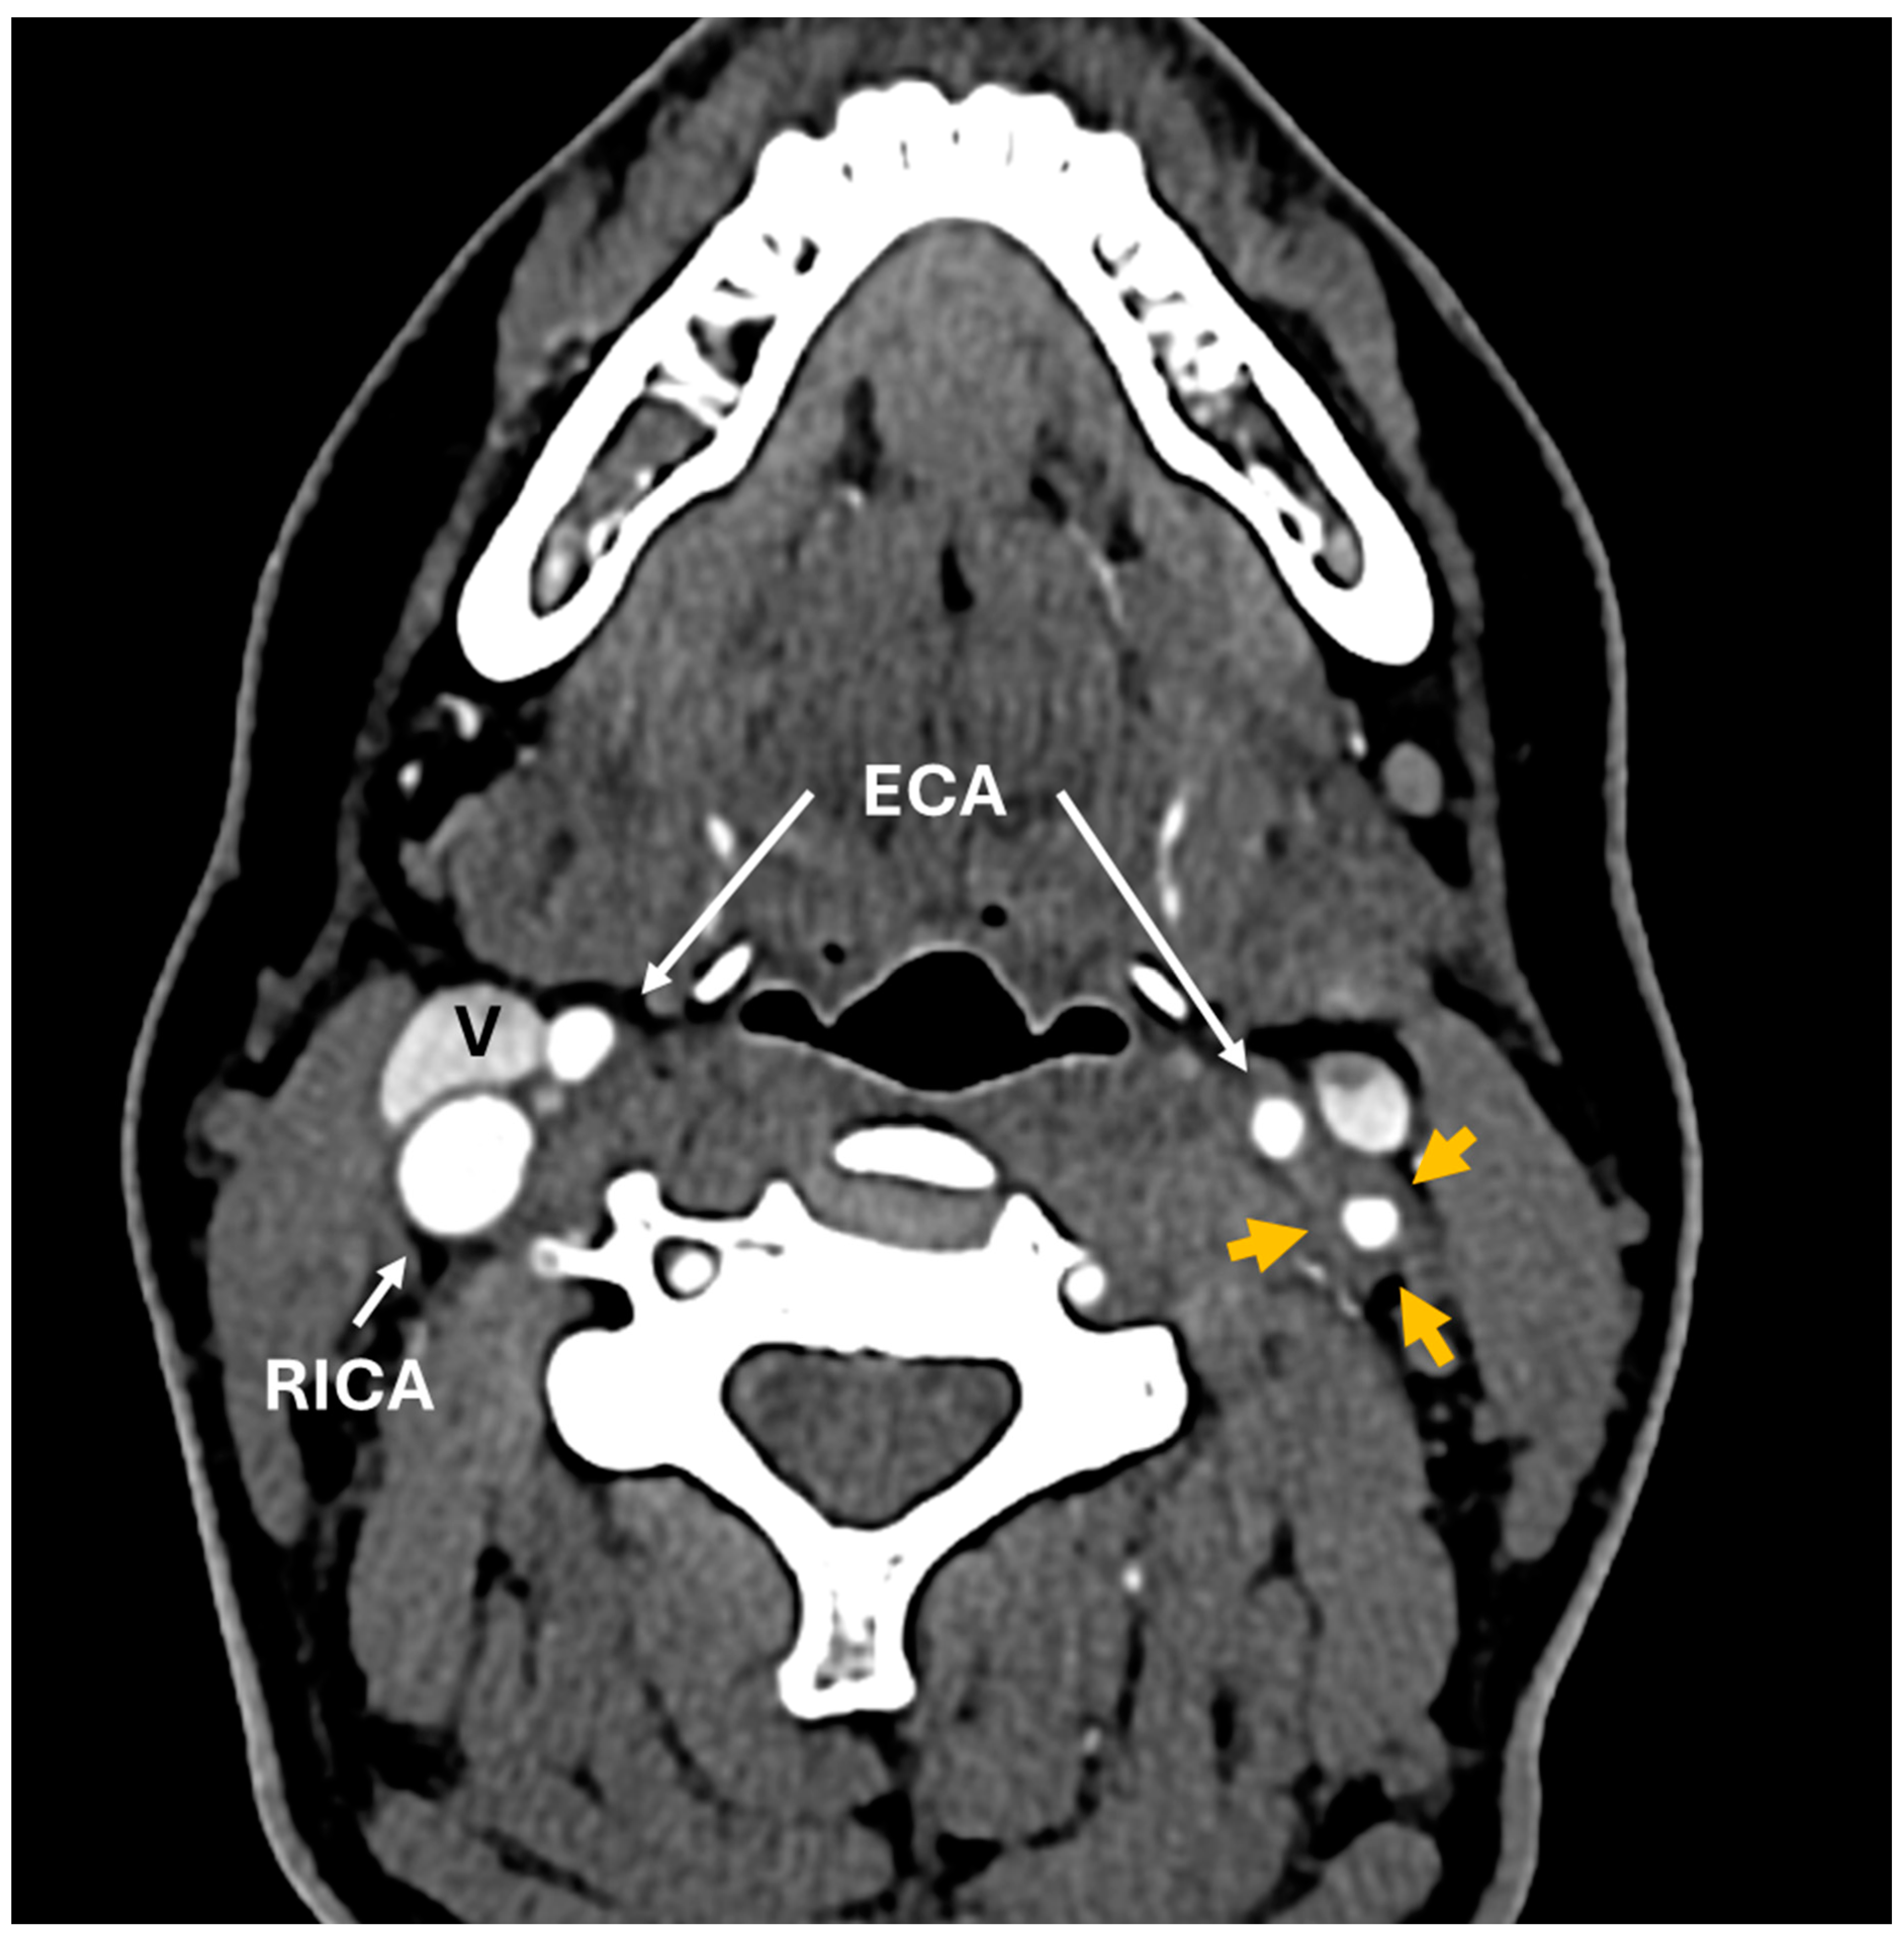

Central Retinal Artery Occlusion Associated with Takayasu Arteritis

Mumtaz, S.; Wilson, C.; Vibhute, P.; Eggenberger, E.R.; Berianu, F.; Abril, A. Central Retinal Artery Occlusion Associated with Takayasu Arteritis. Diagnostics 2024, 14, 1329. https://doi.org/10.3390/diagnostics14131329